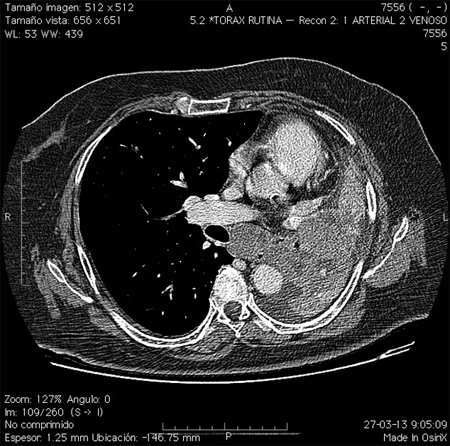

Al ingreso destacaba PA: 150/90, IMC 35 kg/m2, facies cushingoide, hirsutismo de predominio facial, dorso de búfalo, cifosis dorsal y atrofia muscular generalizada. Laboratorio: colesterol total 241 mg/dl, triglicéridos 687 mg/dl, glicemia 320 mg/dl, cortisol plasmático matinal 18 μg/dl, ACTH basal: 58 pg/ml (10-46) y prueba de supresión con 8 mg de dexametasona: 19,1 μg/dl. Resonancia nuclear magnética (RNM) de silla turca y TC de abdomen no muestran hallazgos patológicos. La TC de tórax describe en el segmento lingular inferior del lóbulo superior izquierdo, a nivel periférico, una imagen nodular de 15 mm, bien delimitado que realza heterogéneamente el contraste (Figura 1). En la fibrobroncoscopía no se evidenciaron lesiones y la citología resultó negativa para células neoplásicas.

Figura 1

Se derivó al Instituto Nacional del Tórax, realizándose una toracotomía exploradora que evidenció nódulo de 15 mm sin compromiso del parénquima adyacente. La lesión se resecó completamente y el estudio anatomopatológico informó lesión compatible con tumor neuroendocrino, con cromagranina positiva en 30%, sinaptofisina positiva sobre el 90% y pancitoqueratina positiva en 70% de las células neoplásicas. Estos hallazgos morfológicos e inmunohistoquímicos apoyan el diagnóstico de tumor carcinoide.